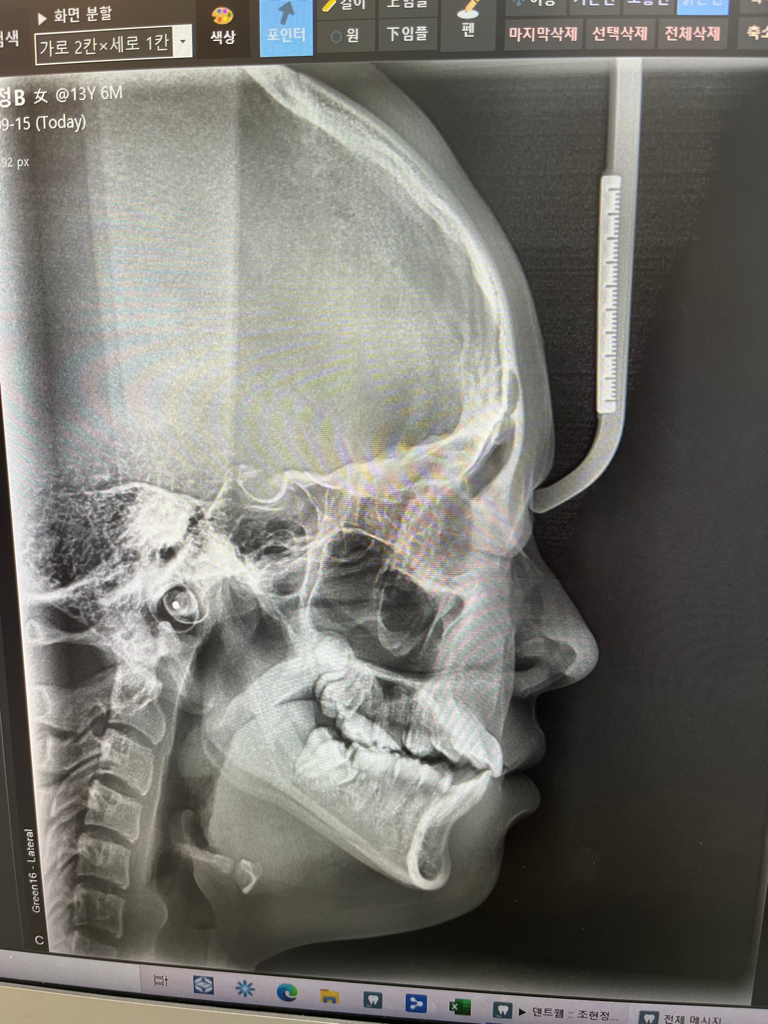

중1딸아이 치아엑스레이에요..꼭 전체교정 필요할까요??

• 1번 째 사진